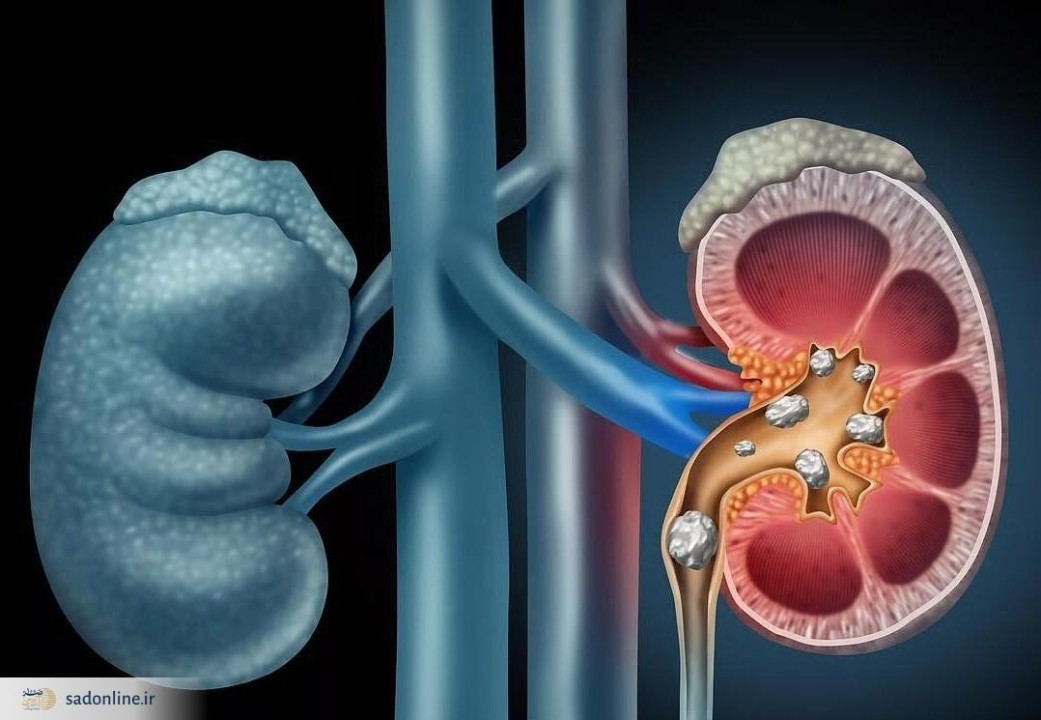

بیماری کلیوی: کلیهها مجبورند برای دفع سدیم اضافی سختتر کار کنند که این امر میتواند به آنها آسیب برساند و خطر تشکیل سنگ کلیه را افزایش دهد.